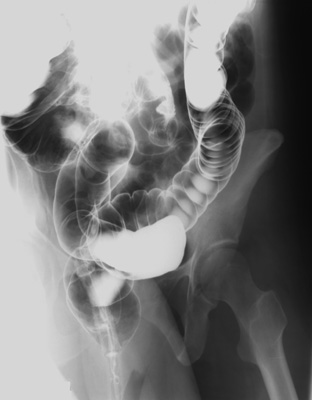

- LPO view of rectosigmoid with 35 degree cephalad central ray on 14"; x 17"

cassette